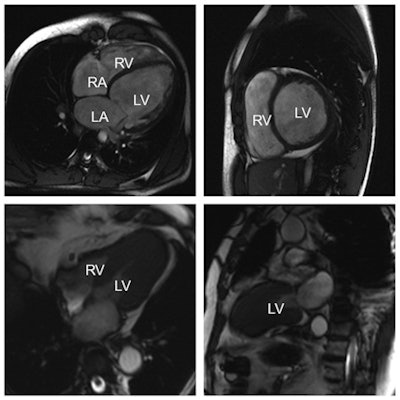

MRI allows radiologists to assess cardiomyopathies and valvular disease with a very high level of precision, even though echocardiography -- especially in skilled hands -- often proves sufficient. "MRI is very good at quantifying the degree of a cardiac valve problem. By using MRI, you can determine the direction and quantity of blood flow, and thereby assess a valvular insufficiency or stenosis with great accuracy," explained Nikolaou, who will chair the Mini Course.

MRI can also be crucial in diagnosing congenital heart diseases, in cases in which ultrasound proves inconclusive. But the problem with MRI in cardiac imaging remains its availability; often limited to universities or dedicated centers, and often with long waiting lists. Congenital diseases are usually assessed in babies or very young children, for whom it is almost impossible to lie still for an MRI for 45 minutes without sedation or general anesthesia, which can present a risk for children. Consequently, radiologists may choose to use CT in younger patients, as it offers rapid diagnosis and has become safer in recent years, with a significant improvement in dose reduction strategies.

MRI and nuclear medicine tests still set the standard for assessing myocardium in ischemic heart disease, as both of these imaging modalities can provide very detailed information on the ischemic myocardium. For instance, in a patient with suspected ischemic heart disease, MRI can reveal typical lesions in the myocardium caused by an infarct.

MRI is also able to help establish whether a myocardial infarction happened recently or a few years ago. "If you use water-weighted images, the presence of edema in the myocardium means that this is a recent infarct," Nikolaou said.

MRI is the first modality in more complex or known cases of coronary artery or ischemic heart disease, for instance if a patient received bypass surgery, suffered known infarcts, or underwent coronary interventions (e.g., with stent implantation). "CT is good for assessing ischemic heart disease at an early stage or for a first diagnosis, but MRI does a better job if it is a more complex case. It gives information on the perfusion defect, old events, if the stent is still patent, etc." he concluded.